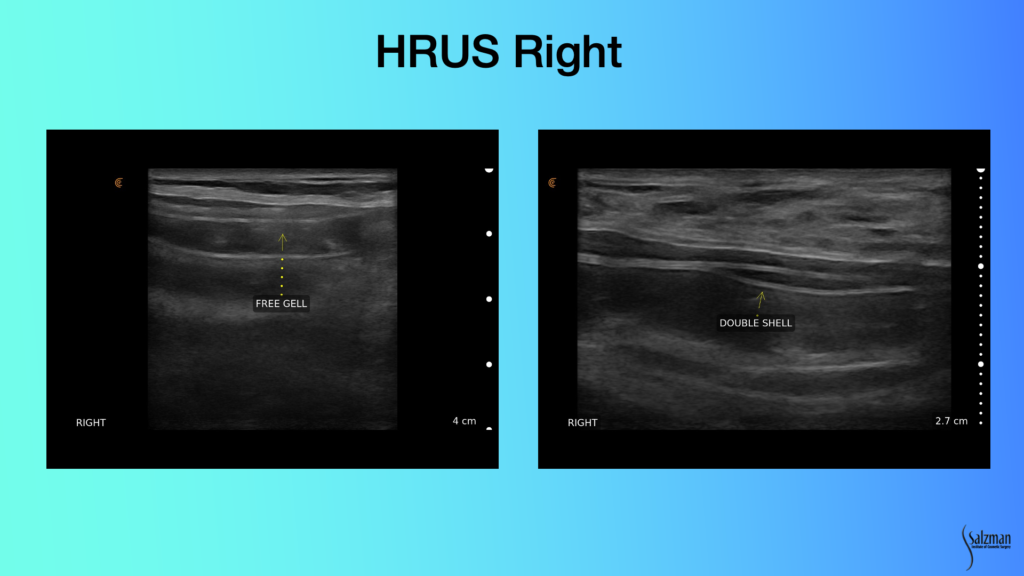

On this left image, you have a double super imposition of the elastomeric shell, with free gel in between, pathognomonic for a broken implant. Same thing on the right. You have double Y-shaped shell like this, and this could be that it’s upside down, if this was not bilaminar. But when they’re both bilaminar with that’s invagination of a broken shell on itself. You’re seeing the shell below the shell. These are both pathognomonically broken implants. You’re never going to miss that with ultrasound.

In contradistinction, look at what we see on the left with our patient. Inside, you still have this cloudy looking material. I don’t think this one’s broken. But looking at the elastomeric shell, those lines are parallel and look pretty good.